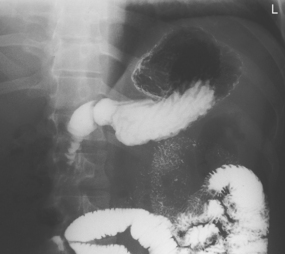

The air-barium distribution within the stomach and large intestine changes with various body positions. By knowing these distribution patterns, one can determine in which body position a radiograph was taken. Air always rises to the highest levels, and the heavy barium settles to the lowest levels (air is black, barium is white).

The fundus is located more posteriorly; therefore in the supine position it would be the lowest portion of the stomach and would be filled with barium.

In both prone and erect positions, the fundus would be filled with air as seen on the drawings below, with a straight air-barium line on the erect.

Fig. 9-31 AP supine Trendelenburg, upper GI (stomach) (Trendelenburg position best demonstrates hiatal hernia).